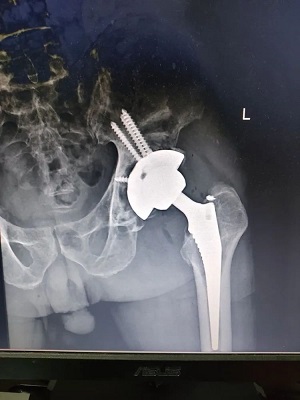

手术后

通过与患者的积极沟通,患者同意开展髋关节翻修术,置换新的人工关节。

骨科(关节外科)经过充分的术前规划和准备,成功为患者开展髋关节翻修置换术。

术后,患者髋关节疼痛消失,没有明显不适,第二天便能扶拐杖下床行走。